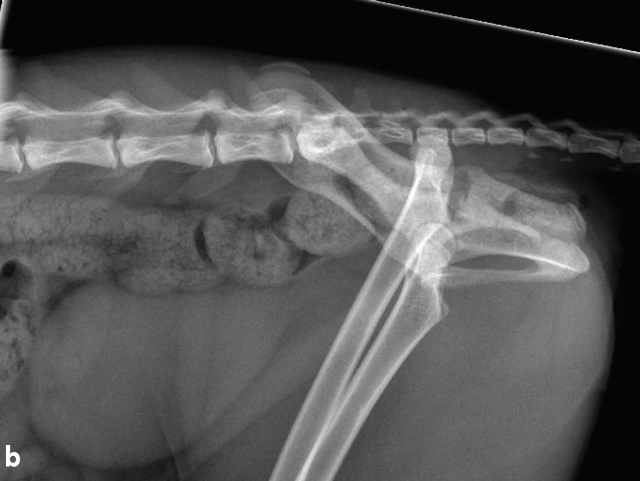

Proximity of the cranial tibial artery to the tibial bone at different angles of stifle extension in the dog: An ex vivo computed tomographic angiographic study

Cranial cruciate ligament disease (CCLD) is the most common cause of pelvic limb lameness in the dog. Tibial plateau levelling osteotomy (TPLO) is one of the most commonly performed procedures to treat CCLD by neutralising cranial tibial thrust and providing dynamic stability to the stifle joint at a standing angle. Excessive haemorrhage during the TPLO procedure has been described as an infrequent but potentially severe intraoperative complication, with a reported incidence of up to 1.6%. Damage to the proximal tibial musculature, cranial tibial artery or its five-way vascular network, or the cranial tibial vein during muscle elevation or performance of the osteotomy has been implicated as the cause of this excessive haemorrhage.1-6 In one study, the authors recommended performing the osteotomy with the stifle in flexion to allow the gastrocnemius muscle to relax and the cranial tibial artery to move caudally, potentially decreasing the risk of injury to the vessel during performance of the osteotomy. However, there have been no studies investigating the proximity of the cranial tibial artery to the tibial bone at different angles of stifle extension in dogs with intact or deficient cranial cruciate ligament. Therefore, the objectives of this study led by Dr Mullins are to: determine the shortest distance between the cranial tibial artery and the tibial bone at different angles of stifle extension in canine cadaveric stifles with an intact CCL and a completely transected CCL; and to investigate whether complete surgical transection of the CCL would result in a significant change in the distance between the cranial tibial artery and the tibial bone at any angle of stifle extension.